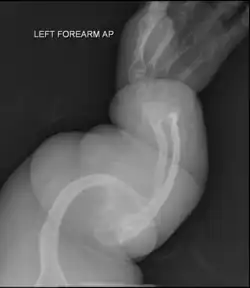

Type II

Collagen is fatally defective at its C-terminus.[5]: 1512 Most cases result in death shortly after birth, or within the first year of life, due to respiratory failure. Another common cause of death is intracranial bleeds from skull fractures present at, or sustained during or shortly after, birth.[5]: 1511 In many cases, the newborn already has multiple broken bones at the time of birth. Type II infants also exhibit severe respiratory problems and have severely deformed bones. Sixty percent of infants die less than 24 hours after being born, and survival after the first year is extremely unlikely and normally requires mechanical ventilation.[57] In the rare cases of infants who survive their first year of life, severe developmental and motor delays are seen; neither of two infants studied in 2019, both aged around two years, had achieved head control, and both required a ventilator to breathe.[58]

Type II is also known as the "lethal perinatal" form of OI,[59] and is not compatible with survival into adulthood.[57] Due to similarly severely deformed bones, sometimes infants with severe type III are wrongly initially classified as type II; once long-term survival is shown, they are considered as having type III instead.[5]: 1511 [60]

Diagnosis is typically based on medical imaging, including plain X-rays, and symptoms. In severe OI, signs on medical imaging include abnormalities in all extremities and the spine.[97] As X-rays are often insensitive to the comparatively smaller bone density loss associated with type I OI, DEXA scans may be needed.[5]: 1514

An OI diagnosis can be confirmed through DNA or collagen protein analysis, but in many cases, the occurrence of bone fractures with little trauma and the presence of other clinical features such as blue sclerae are sufficient for a diagnosis. A skin biopsy can be performed to determine the structure and quantity of type I collagen. While DNA testing can confirm the diagnosis, it cannot absolutely exclude it because not all mutations causing OI are yet known and/or tested for.[83]: 491–492 OI type II is often diagnosed by ultrasound during pregnancy, where already multiple fractures and other characteristic features may be visible. Relative to control, OI cortical bone shows increased porosity, canal diameter, and connectivity in micro-computed tomography.[98] OI can also be detected before birth by using an in vitro genetic testing technique such as amniocentresis.[99]